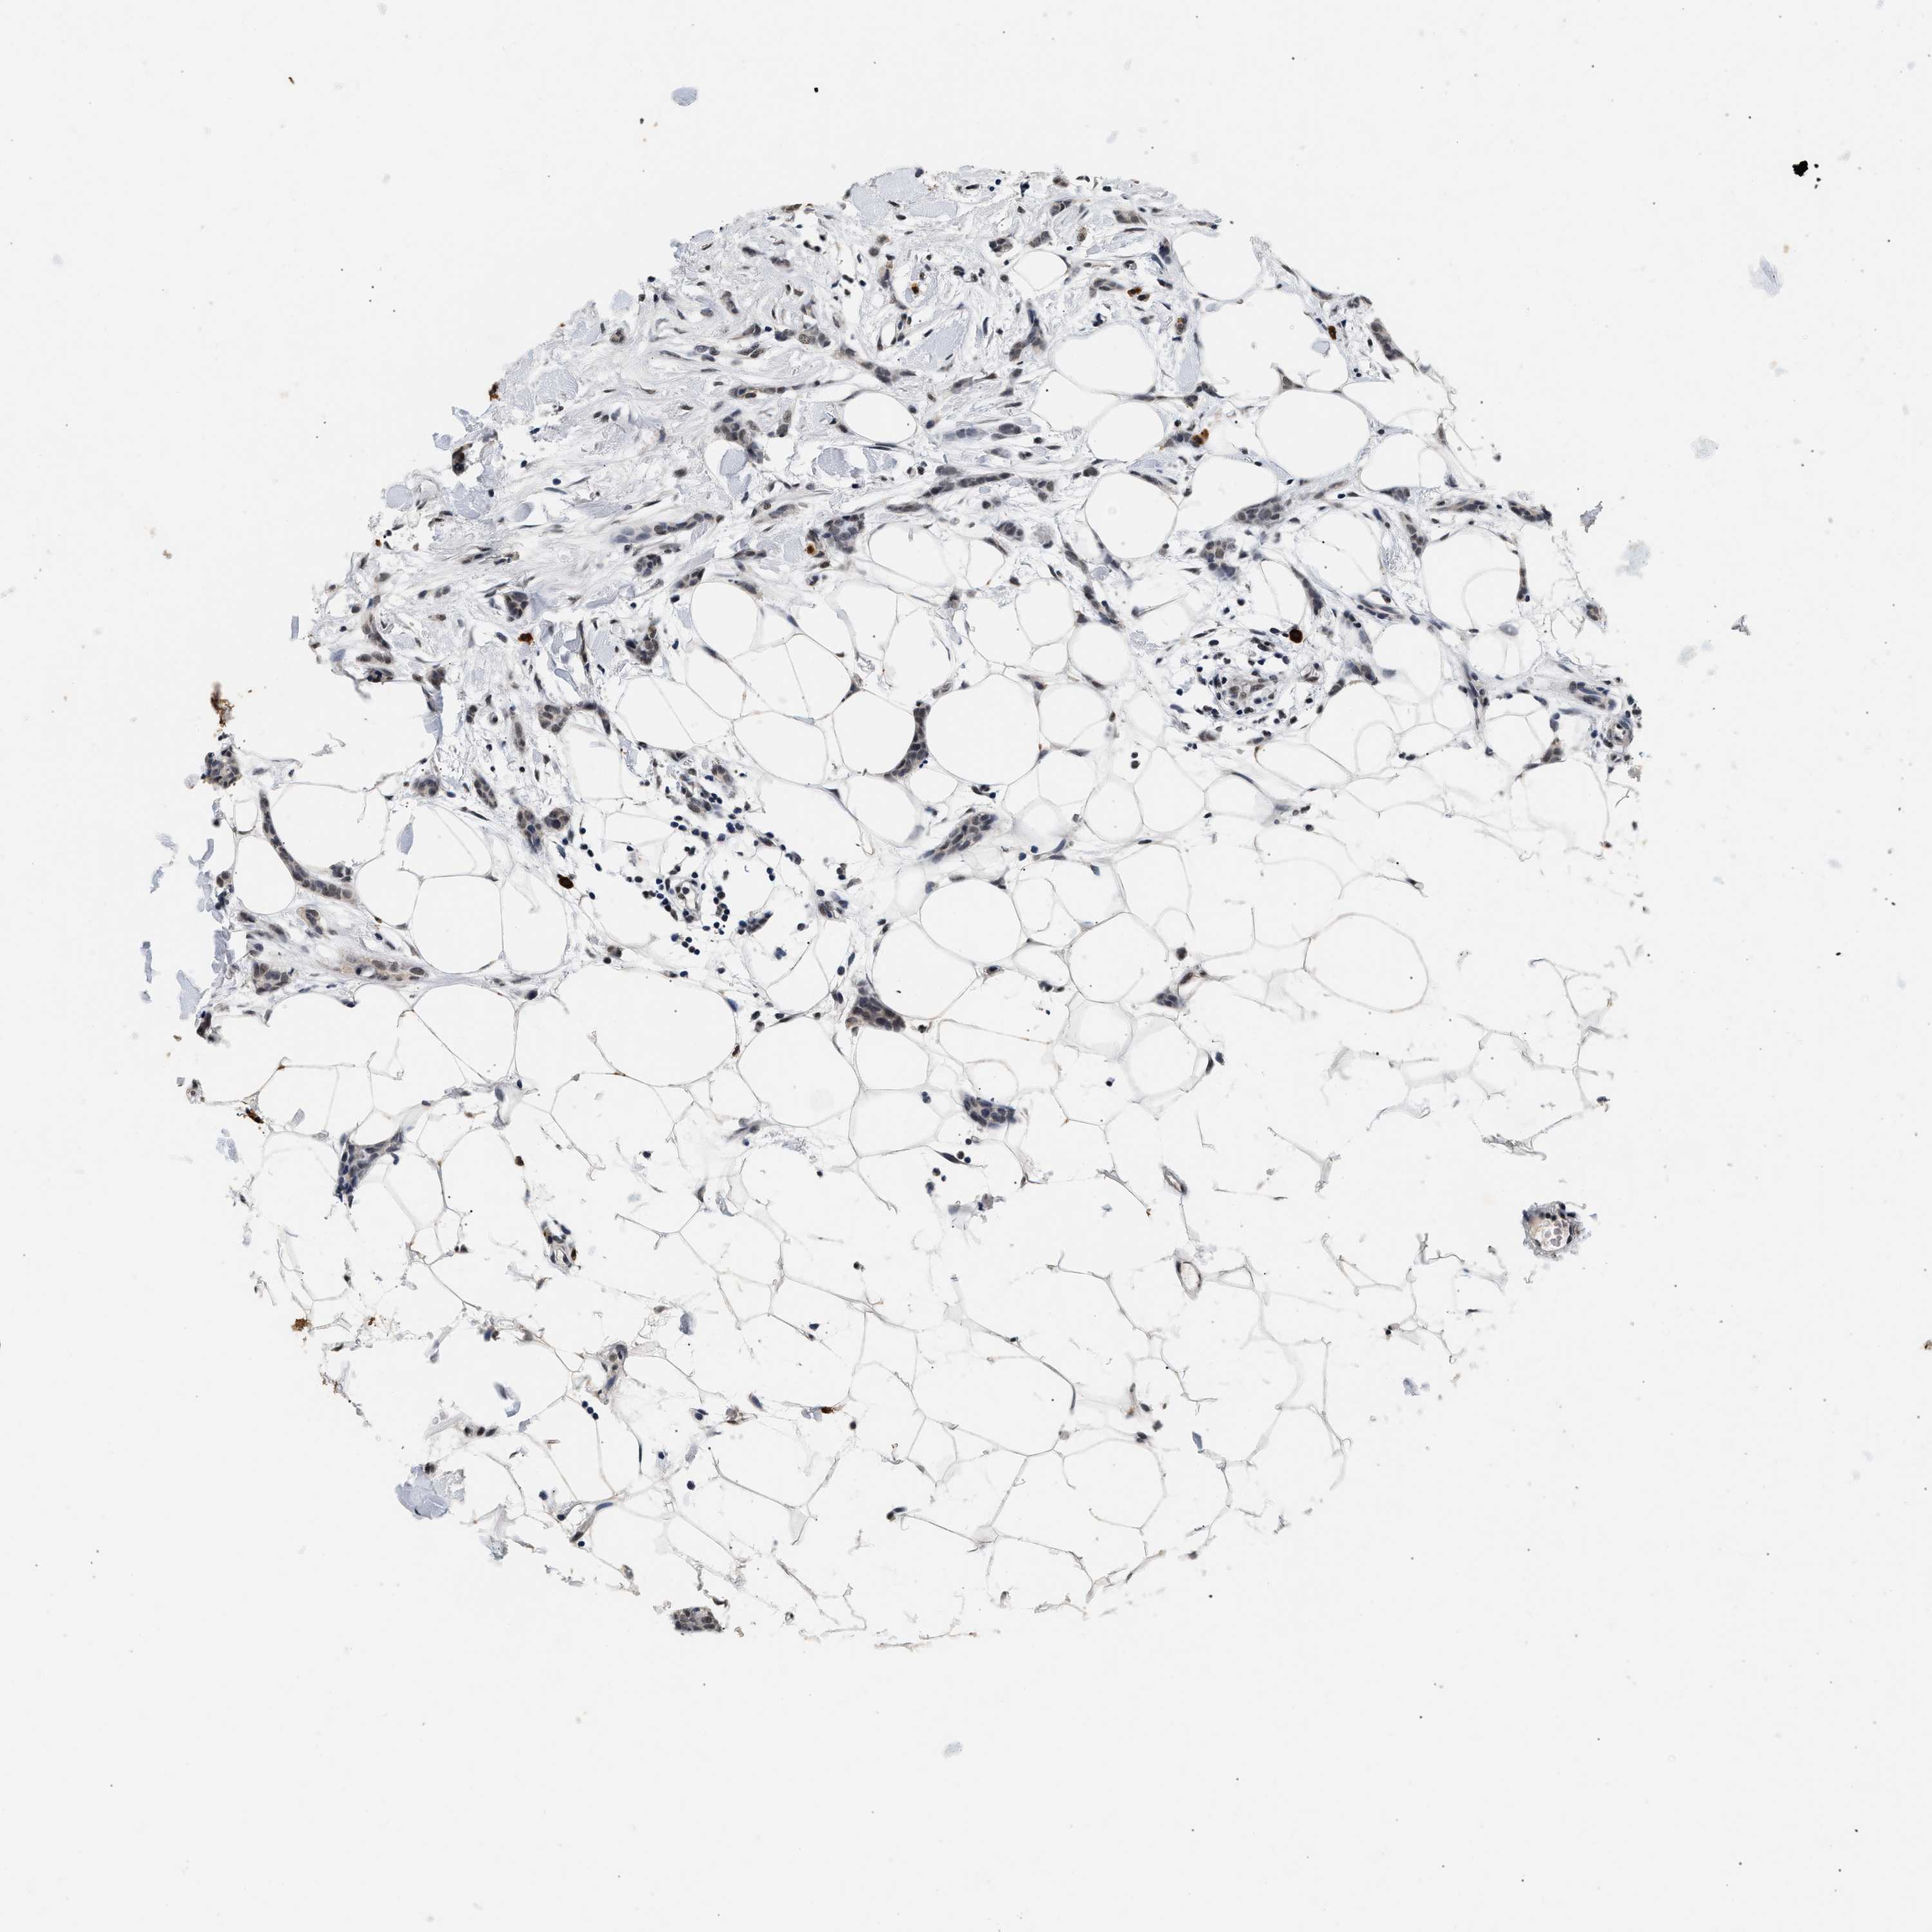

CANCER BREAST CANCER Show tissue menu

BRCA TCGA BRCA VALIDATION PROTEIN EXPRESSION